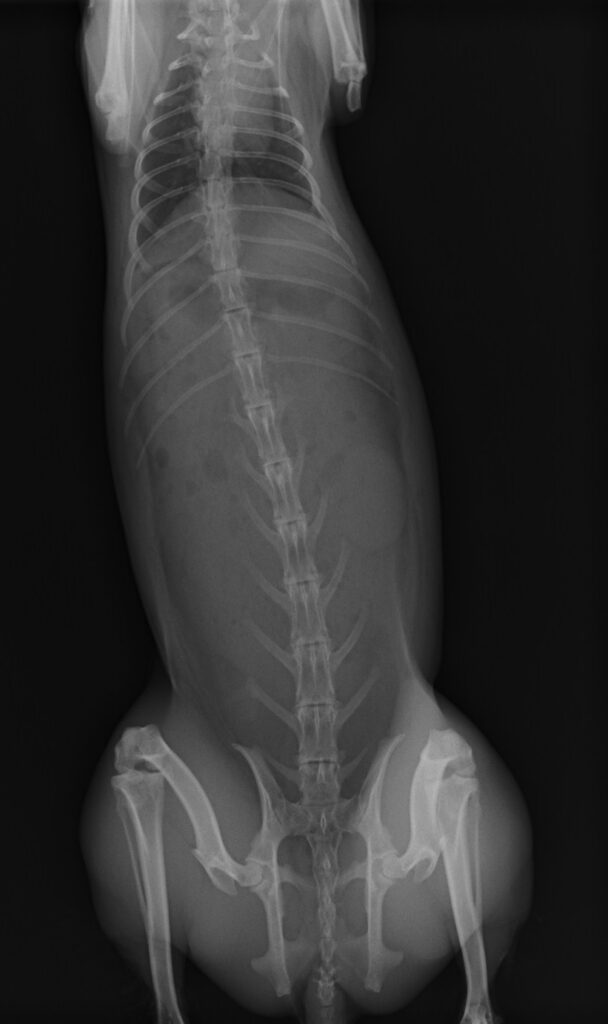

そしてレントゲンです。

前後と左右、二方向撮影します。

心臓の大きさ 肺が白くないか

骨格異常がないか 消化管ガスはないか

何か他に映ってないか

チェックします。